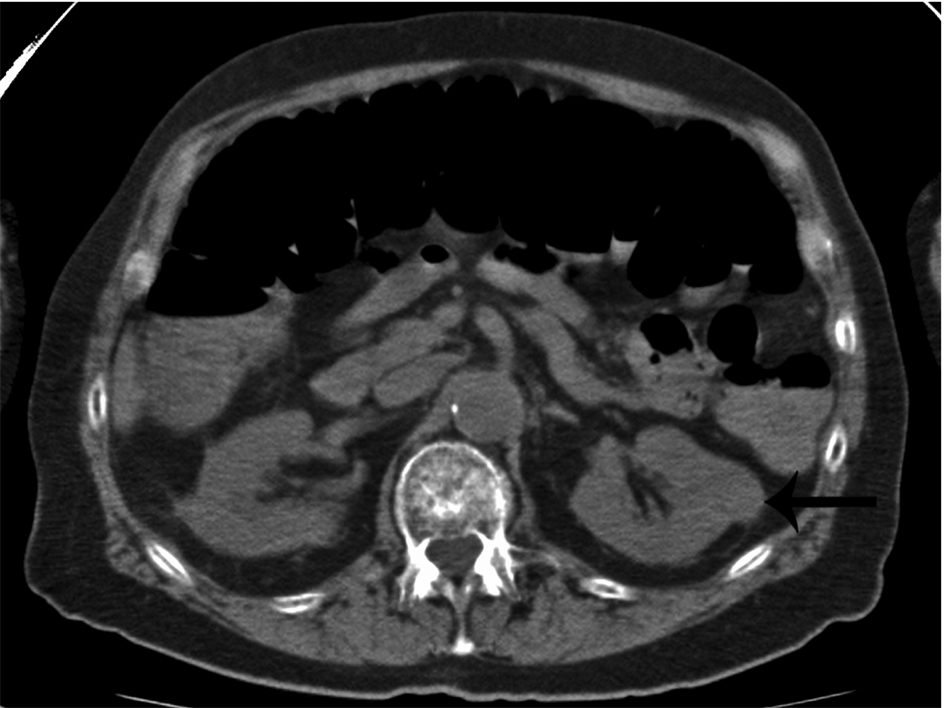

The 72 MM patients who had both CSS and WBCT performed within 30 days of the first autologous HCT are listed in Table 1 with their disease characteristics and treatment details. Forty one patients (57%) were in group 1 and had more findings on WBCT than CSS; 31 patients (43%) were in group 2 and had no differences in the two imaging techniques; 9 of these patients were in group 3 and had no bone lesions on either modality; and 5 patients (group 4) had lesions only identified by WBCT and not on CSS. Group 5 consisted of 14 patients (19%) who had a normal CSS and 5 of these patients had bone lesions detected by WBCT alone. Examples are shown in Figure 1. Two patients had incidental renal masses identified which were surgically resected and found to be renal cell carcinoma (one example is shown in Fig. 2). Table 1 lists the patients in groups 1 and 2 who had tandem autologous or allogeneic HCT as well as salvage autologous or allogeneic HCT and/or maintenance therapy and they are similarly distributed between the two groups. Table 2 lists the patient and disease characteristics of Group 5 (negative CSS) compared to all other patients. No statistically significant difference was found between Group 5 and all the other patients including stage of MM, time from diagnosis to transplant, lines of chemotherapy prior to transplant or adverse cytogenetics. Having a negative CSS was the only significant factor on multivariate analysis for PFS and this was also maintained on multivariate analysis for OS (Table 3, 4). Additional significant factors on multivariate analysis for OS were DS stage IIIB and ISS II.

![]() Click for large image | Figure 2. Incidental finding of a non-cystic, exophytic left renal mass in a patient with multiple myeloma (arrow). This mass was later found to be a renal cell carcinoma. |

Whole body multidetector computed tomography (WBCT) has been shown to be more sensitive in detecting small osteolytic lesions (< 5 mm) in the spine as compared to whole body MRI and 18F-fluorodeoxyglucose positron emission tomography (FDG-PET) [11, 12]. WBCT can detect early small lytic bone lesions in the vertebral bodies, scapulae, ribs and sternum (Fig. 1) and determine the fracture risk better than CSS [21, 22]. In addition, over 30% of trabecular bone loss is needed before lytic bone lesions can be detected by plain films [21, 22]. This is significant because the most common areas of myelomatous bone disease are in the vertebrae, ribs, skull and shoulders [23]. WBCT is faster without a need for repositioning frail patients with bone pain; however, the cost of the WBCT is substantially more than CSS (at our institution WBCT costs $2,822 US dollars in comparison to $607 US dollars for CSS). The slightly higher radiation doses of the WBCT are not usually an issue in a disease that mainly affects the elderly. WBCT is nonspecific for osteopenia or osteoporosis. Although there is a risk of renal insufficiency if intravenous iodinated contrast is used in patients with MM, especially those with Bence-Jones proteinuria, this is not an issue in standard noncontrast WBCT. Also in our study, 2 patients were diagnosed with renal cell carcinoma after the finding of incidental renal masses on WBCT (Fig. 2).